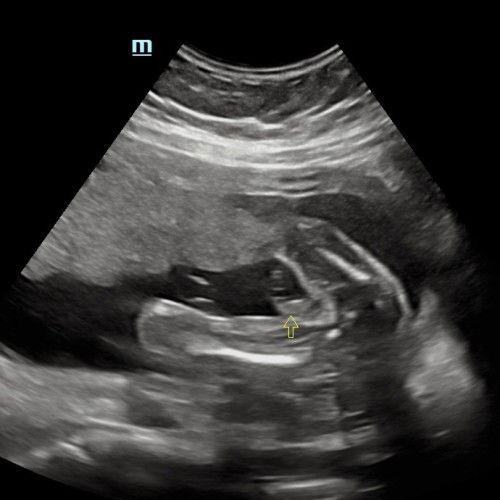

Nampak Girl/Boy?

Pinjam mata Mommy semua nampak apa? doc kata boy tapi sebab kedudukan dia tak diam dalam perut ni je dapat 🤣 mohon bantuan ye tq 🥰 #bantusharing #ingintahu

Baby boy sis nmpk bntuk pistol tu🤣